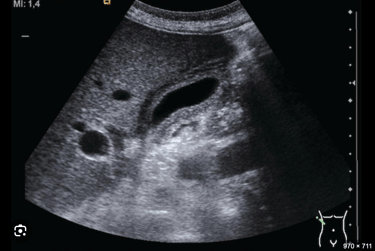

Our abdominal course unfolds as a systematic, high-yield survey of visceral imaging, Doppler interpretation, and clinical reasoning.

Early sessions focus on image ergonomics and machine optimization, giving learners tactile confidence and geometric orientation to three-dimensional anatomy across the abdomen. From there, we move through a comprehensive organ-by-organ protocol, teaching learners to interpret anatomy, echogenicity, Doppler blood flow, and physiologic relationships with clarity.

Hands-on practice is continuous. Learners repeatedly apply Doppler to vascular structures, correlate findings with pathology, and learn how to document each organ and vascular bed in a methodical way.